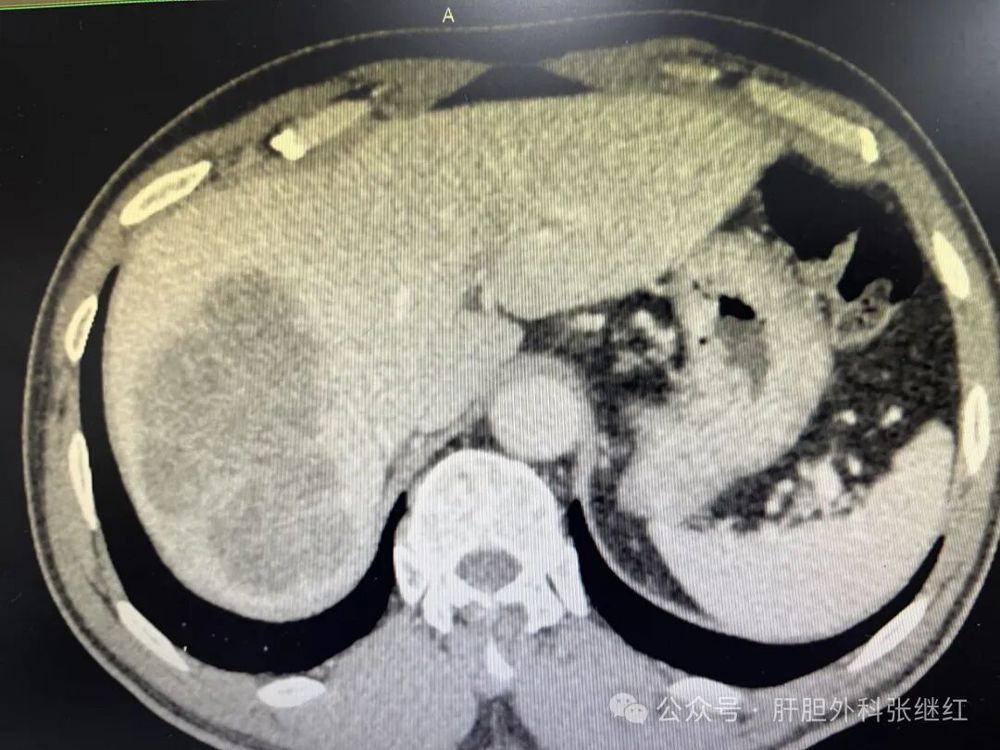

71435272e89b47ad827d11eddfc4334e.jpg

术后一周CT